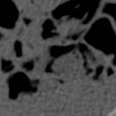

Task Generation. The CT database in [45] contains CT scans of a deceased piglet. The scans are produced using a normal dose of tube current (100%) and reduced doses. We use the doses of 10% and 5% because they include substantial amount of noise, where each dose set has 850 images of size . Following the data set protocol [45], 708 of those images are selected for training and 108 for testing. During training, each task consists of synthetic images generated by simulating reduced dose CT images by adding Poisson and Gaussian noise to the sinograms of the normal dose CT images, as in , where , , with denoting the Poisson distribution, representing the process to generate the sinogram or the fan-beam projected data [48] from the clean CT image , denoting the read-out electronic noise represented by the Gaussian distribution with mean and variance , and denoting the X-ray source intensity or a blank scan factor that controls the noise level. We create the tasks with , namely one per blank scan factor, where we use the following factors . Consequently, each factor contributes to the generation of a different task. To simulate the effect of the Gaussian noise, we add noise directly on the CT image . The Gaussian task is represented by Gaussian noise with , where denoting uniform distribution in . The result is the noisy image for and . Finally, we keep images for the meta-learning for each reduced dose set. The rest of the images are used for evaluation.

Model. We use a residual encoder-decoder architecture from [12] that has been proposed for low dose CT denoising [45]. The network consists of a 10-layer convolutional neural network with input and output sizes of . The activation functions are all ReLU, except for the last layer that is linear. The optimization algorithm is Adam [19] with learning rate . The inner loop has 20 epochs with mini-batch size 20. The outer loop runs for 1000 epochs with step-size and the number of fine-tuning samples .

Results. We evaluate CT-Scan denoising on tube current with doses and , where smaller percentage denotes more noise – results are summarized in Table 1. We generate from 4 to 8 Gaussian and Poisson tasks, with each task representing an individual noise model. Notice that we also applied Gaussian and Poisson noise, at the same time, on an image as another task, but the performance was not as good as sampling independently. In the case of task combination (e.g. 4 Gaussian and 4 Poisson), we equally sample tasks from both noise models. We attempted to generate less than 4 and more than 8 tasks, but there was not a considerable performance difference.

The same evaluation is performed for the supervised- and transfer-learning. Comparing with these two algorithms, it is clear that our approach delivers the highest PSNR. Although the results from transfer learning are closer, the difference is significant based on the t-test as we show in Sec. 4.4. Since this is the only experiment where we have access to a relatively large training set containing pairs of clean and real noisy data, we check the upper bound performance for our approach, which is the supervised learning performance using this large training set. Note that such full supervision violates one of our three assumptions mentioned in Sec. 1 – in particular, the one regarding the availability of a large number of training samples. Supervised learning achieves 40.28dB for and 38.84dB for , when trained with clean and real noisy training data. Our results in Table 1 indicate that we are close to this upper bound, although we train with synthetic training data. To further explore our approach, we meta-train it with clean and real noisy training data. Notably, our meta-denoising reaches 40.47dB for and 38.31dB for . This result shows the potential of meta-learning to become the standard training algorithm for the task of denoising. We present visual results in Fig. 1.